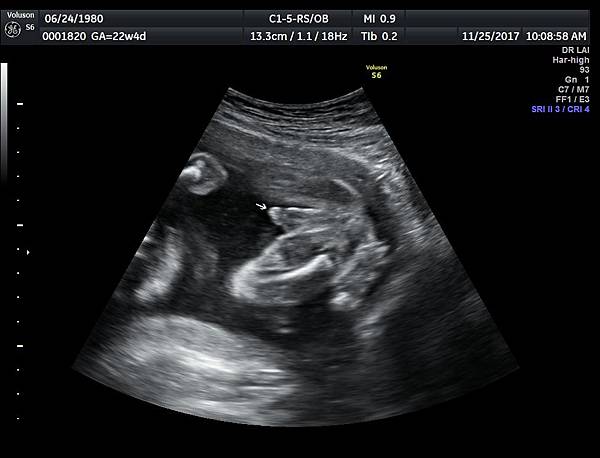

今天下午一位28歲第一胎的孕婦來診所做超音波檢查,之前他們一直認為懷的是女兒(檢查前資料顯示胎兒是女生);今天我的診斷胎兒是男生,但是懷疑有尿道下裂的問題(附圖 1~4),我的建議是抽羊水做染色體基因檢查,除了確定性別之外,也可以排除是否合併基因異常。

2018年3月的一位孕婦,產檢期間醫師也覺得比較像女生,羊水報告卻是男生,經過我的檢查,診斷是胎兒懷疑有尿道下裂(附圖 5.),產後證實是尿道下裂(附圖 6.7.)。

尿道下裂的個案,產檢時常被看成女生,所以做高層次檢查時一定要看清楚胎兒性別,即使父母表明不要知道胎兒性別,我一樣要看清楚性器官,只要不主動告知父母胎兒性別即可,這樣的堅持就是要排除尿道下裂;女寶寶的特徵是典型三條線(附圖 8.),男寶寶需要看到突出的生殖器(附圖 9.)。

診斷尿道下裂常用的鬱金香sign(tulip sign)(附圖 10.11.),它的特徵就是龜頭陷入陰囊中間,胎兒如果是男生,一定要看到龜頭離開陰囊,這樣就沒有問題,每次遇到尿道下裂的個案時,我都會有一個感觸,男生如果能站著尿尿都要很感恩。